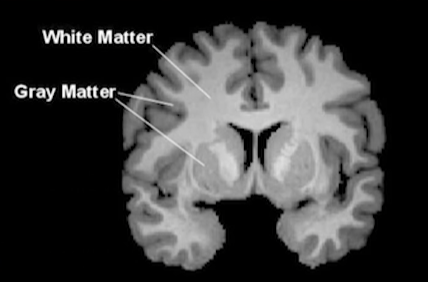

- 大脑神经细胞分为:

图1-3 - 灰质(神经细胞)

- 白质(神经纤维)